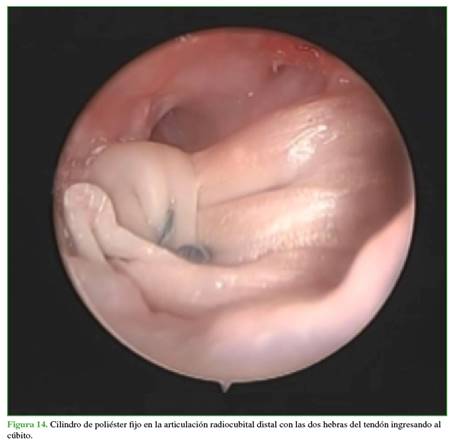

Se comprueba que la colocación y el anclaje del injerto sean correctos mediante la pronosupinación completa traccionando con el palpador de proximal a distal para comprobar la tensión del injerto (Figura 14).